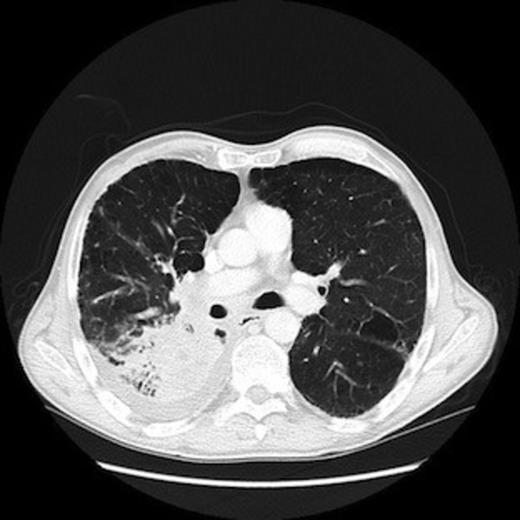

A CT scan showed an 8.8cm soft tissue mass occluding the right lower lobe bronchus (Fig. 4), bilateral nodules suspicious of pulmonary metastases, and lymphadenopathy in the right hilar, paratracheal and anterior mediastinal regions. In addition there were foci of reduced attenuation in the liver and thoracic skeletal metastasis with imminent cord compression at T4.

CT scan of chest demonstrating primary lung tumour in the right lower lobe.